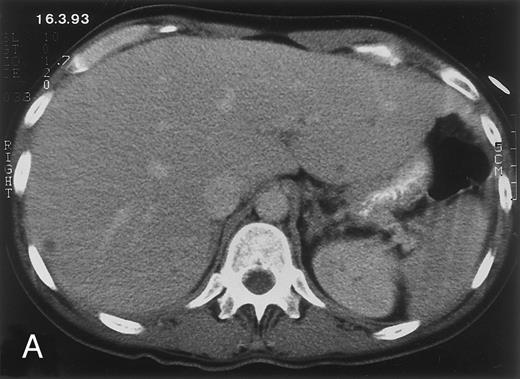

Radiologic evolution in patient A. (A) Postcontrast abdominal CT scan on March 16, 1993 shows multiple small hypodense areas in all segments of the liver, suggestive of hepatic candidiasis. Seven days previously, the patient had recovered from severe neutropenia after the first cycle of chemotherapy for AML. (B) On April 23, 6 days after the neutrophil count had dropped below 500/μL in the second cycle of chemotherapy, there is no evidence of focal lesions on postcontrast CT scan. (C) On June 18, when neutrophils were normalized for 46 days, CT scan again shows multiple small abscesses.

(D) On August 23, 15 days after the neutrophil count had dropped below 500/μL in the third chemotherapy cycle, focal liver lesions clearly decreased in size and number. (E) On September 30, 35 days after neutrophil recovery, multiple hepatic abscesses are seen (arrowhead). To show maximal extent of lesions the scan shown is at a slightly different level. (F) On June 16, 1994, 230 days after neutrophil recovery, the CT scan has normalized.

Evolution of fungal lesions on CT scans during and after neutropenia is summarized in Table 2. Figure 1 (patient A) and Fig 2 (patient B) serve to illustrate Table 2.

In three patients, multiple round lesions were seen on postcontrast CT scans of the abdomen in the liver and the spleen, while in two cases, lesions could only be seen in the liver (Table 2). Following the diagnosis of disseminated candidiasis, these lesions decreased in size and visibility during subsequent neutropenia in three patients (compare Fig 2A and B) and disappeared completely in two patients (compare Fig 1A and B). The numbers of days of severe neutropenia (neutrophils <500/μL) at the time the CT scan was performed are listed in Table 2. After recovery from neutropenia and despite continued antifungal therapy, the size and visibility of the lesions increased again (Fig 1C). Similarly, the number of days since recovery from severe neutropenia (neutrophils >500/μL) are listed in Table 2. In two of three patients treated with another cycle of myeloablative chemotherapy, this waxing and waning pattern of radiologic lesions could be seen again (Fig 1D and E). In all patients, lesions eventually disappeared (Figs 1F and 2D) after prolonged antifungal therapy.

Diagnosis of disseminated candidiasis is often difficult, because cytologic, histologic, and microbiologic findings may remain negative.1 3 Biopsy confirmation of diagnosis was achieved in four of five cases. The initiation of antifungal treatment before biopsy in patient A may have contributed to the negative pathologic findings. Nevertheless, the typical presentation with right upper abdominal discomfort, persistent fever after resolution of prolonged neutropenia, elevated C-reactive protein level, and typical multiple lesions on CT scan (Fig 1A), as well as the disease course with eventual total disappearance of lesions under antifungal treatment, was sufficient evidence to establish the diagnosis in patient A.